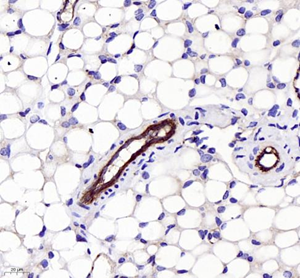

| Immunohistochemistry of paraffin embedded mouse Skeletal muscle using CD31 (GB11063-3) at dilution of 1:400 (400x lens) |